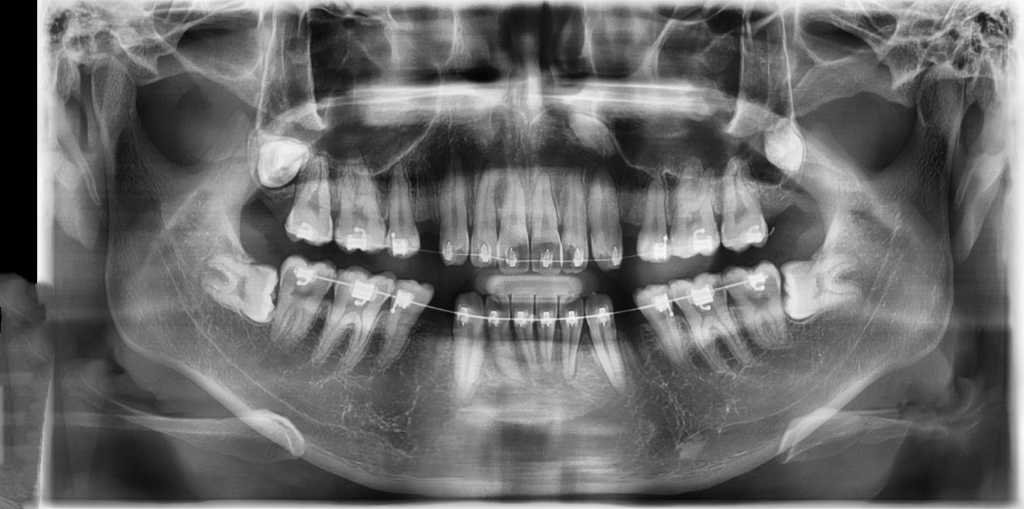

• 2번 째 사진

치아 사이가 전체적으로 많이 썩어 잇네요. 왼쪽 아래 뒤에서 두번쨰 #36번 치아는 충치가 많이 진행된거 같습니다. 신경치료 가능성이 높아보이긴 하네요.

들으신대로 다른 치아는 크게 문제는 아니지만 36번 치아의 경우에는 신경치료 가능성이 높습니다.